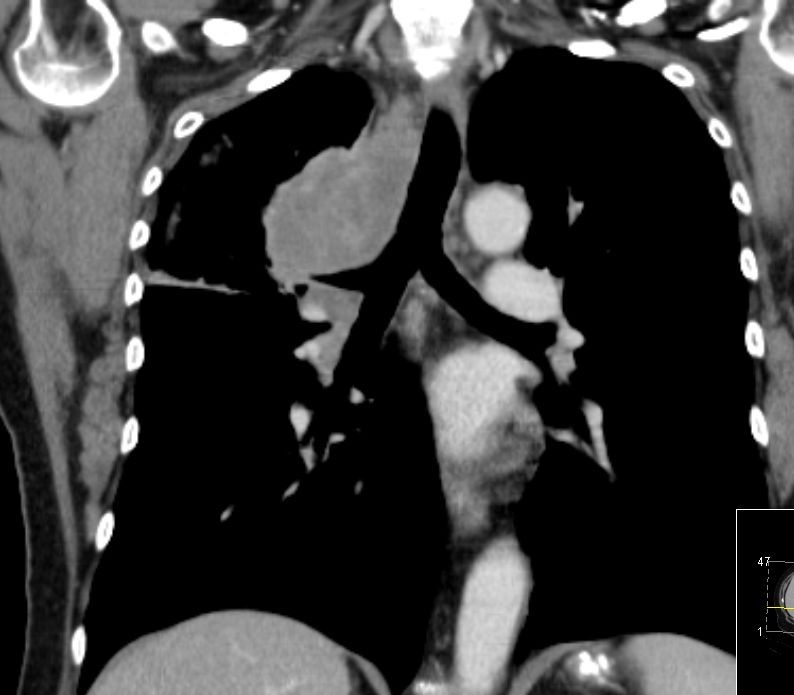

zentrales, kleinzelliges Lungenkarzinom rechter OL mit Infiltration des Mediastinums T4 N3 M1 oss ? 68jährige Patientin im reduzierten AZ und normalen EZ. Unsicherer Gang bei Kreislaufstörungen. Belastungsdyspnoe. Deutliche Leistungsschwäche. Supraklavikulargruben: links frei, rechts auffälliger Tastbefund. ![]() |

![]() | ||